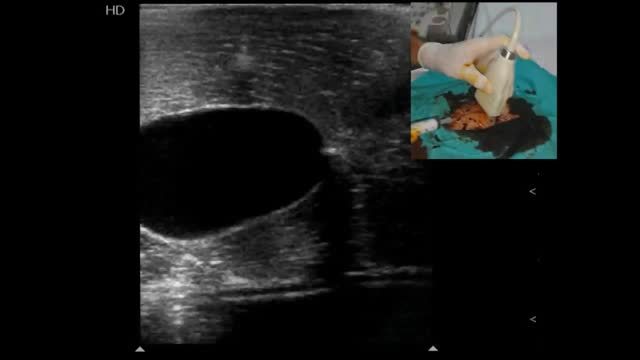

Confirming proper vessel cannulationAlong with detecting direct and indirect signs of vessel cannulation and observing blood returning, it is recommended to have the guidewires shown into the target vessel when used2,7 (Video 7). This practice allows to finally advance the catheter into the target vessel and not in adjacent tissues if it is unintentionally placed in a wrong position. The final position of the catheter should also be directly and indirectly displayed (Video 8).2,7 In peripheral venous cannulation, an agitated saline flush (10ml) passed through the catheter allows to display microbubbles running into the vessel and thus guaranteeing its adequate position and function7 (Video 8). For central venous cannulation, an agitated saline flush is injected through the catheter, normally observing the microbubbles flowing in the right atrium7 within 1–2s16 in simultaneous echocardiographic assessment in subcostal or apical 4-chamber views, performed with a phased-array or a convex probe.

Ultrasound-guided vascular cannulation: the procedure itselfStatic vs real-time techniquesOnce a target vessel is selected, cannulation can be executed using an static technique (US-guided vascular location and skin marking but without using real-time US guidance) (Video 1) or using a dynamic or real-time technique, consisting in observing the screen for direct or indirect signs of the needle entering into the vessel.2,7 (Videos 2, 3 and 4). Both US techniques are more successful for cannulation in comparison with the landmark technique.2,7 When comparing the static and dynamic techniques, the latter has demonstrated a better performance for vascular cannulation compared to the former.2,7 Advantages of the static technique is that it does not require sterile covers for the probe or a needle-screen coordination by the operators. On the other hand, in the real-time technique, cable and probe protection (as well as using sterile US gel) is needed to maintain a sterile technique, the latter usually resulting in some loss of resolution. Additionally, dynamic techniques require a perfect coordination between needle insertion, screen observation and the evaluation of blood returning from the needle, skills that necessarily require proper training and learning curve.